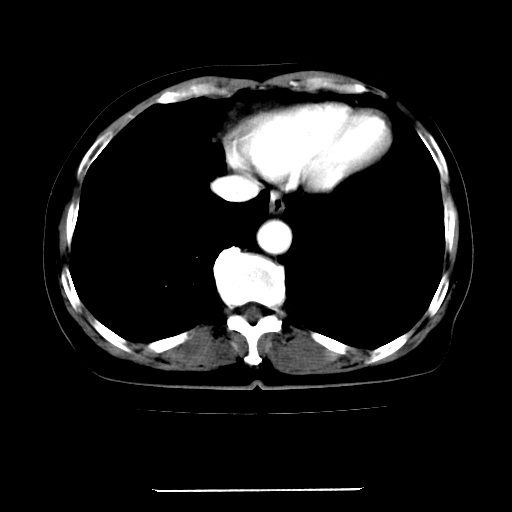

标题: CT22301:女,67岁,上腹部疼痛一周伴皮肤黄染,无发热。 [打印本页]

女,67岁,上腹部疼痛一周伴皮肤黄染,无发热。

左叶肝内胆管结石,并远端肝内胆管扩张。

考虑:肝内胆管结石继发肝内胆管扩张,右肾旋转不良。

肝内外胆管结石并肝内胆管扩张。

建议薄层观察,除外肝门部胆管细胞癌

考虑肝胆管癌;胰头占位?【形态失常,体积增大】

1、肝门高密度影下层面和胰头层面可见轻度胆管扩张,而静脉和延迟期均未见扫描完胰头,不能完全排除胰头占位。2、肝门部高密度影,考虑钙化或结石。

考虑肝门胆管癌伴门脉左支受侵包埋,建议mrcp进一步检查。